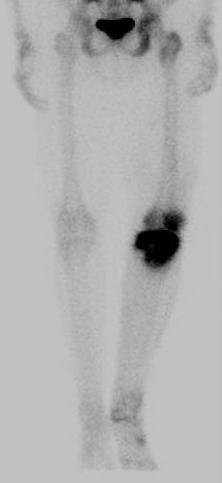

Bone Scan

1. Identify margins for resection / identify skip lesions

2. Identify metastatic disease

Bone scan with isolated disease

Bone scan metastasis